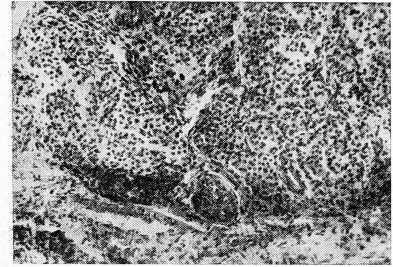

Но в условиях длительного дефицита йода (18—24 мес.) у крыс в щитовидной железе развиваются аутоиммунные процессы (лимфоидная инфильтрация стромы, массивное разрастание соединительной ткани в ней); формируется паренхиматозный зоб (рис. 1).

Рис. 1. Щитовидная железа крысы, получавшей добавку 0,003 мкг/г хрома к рациону в течение 18 месяцев. Объяснение в тексте. × 200.